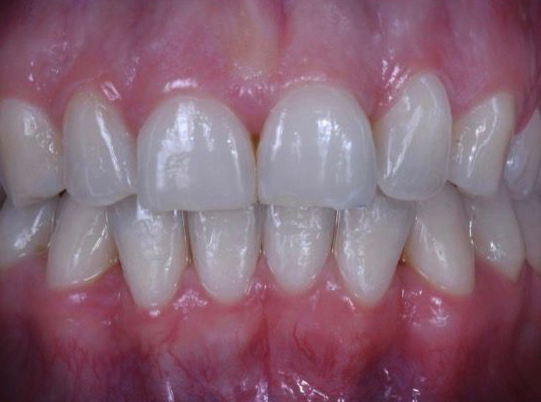

Invisalign and Composite Bonding

This is a case of toothwear caused by teeth crowding. Orthodontic treatment helped to restore the aesthetic and function of the front teeth.